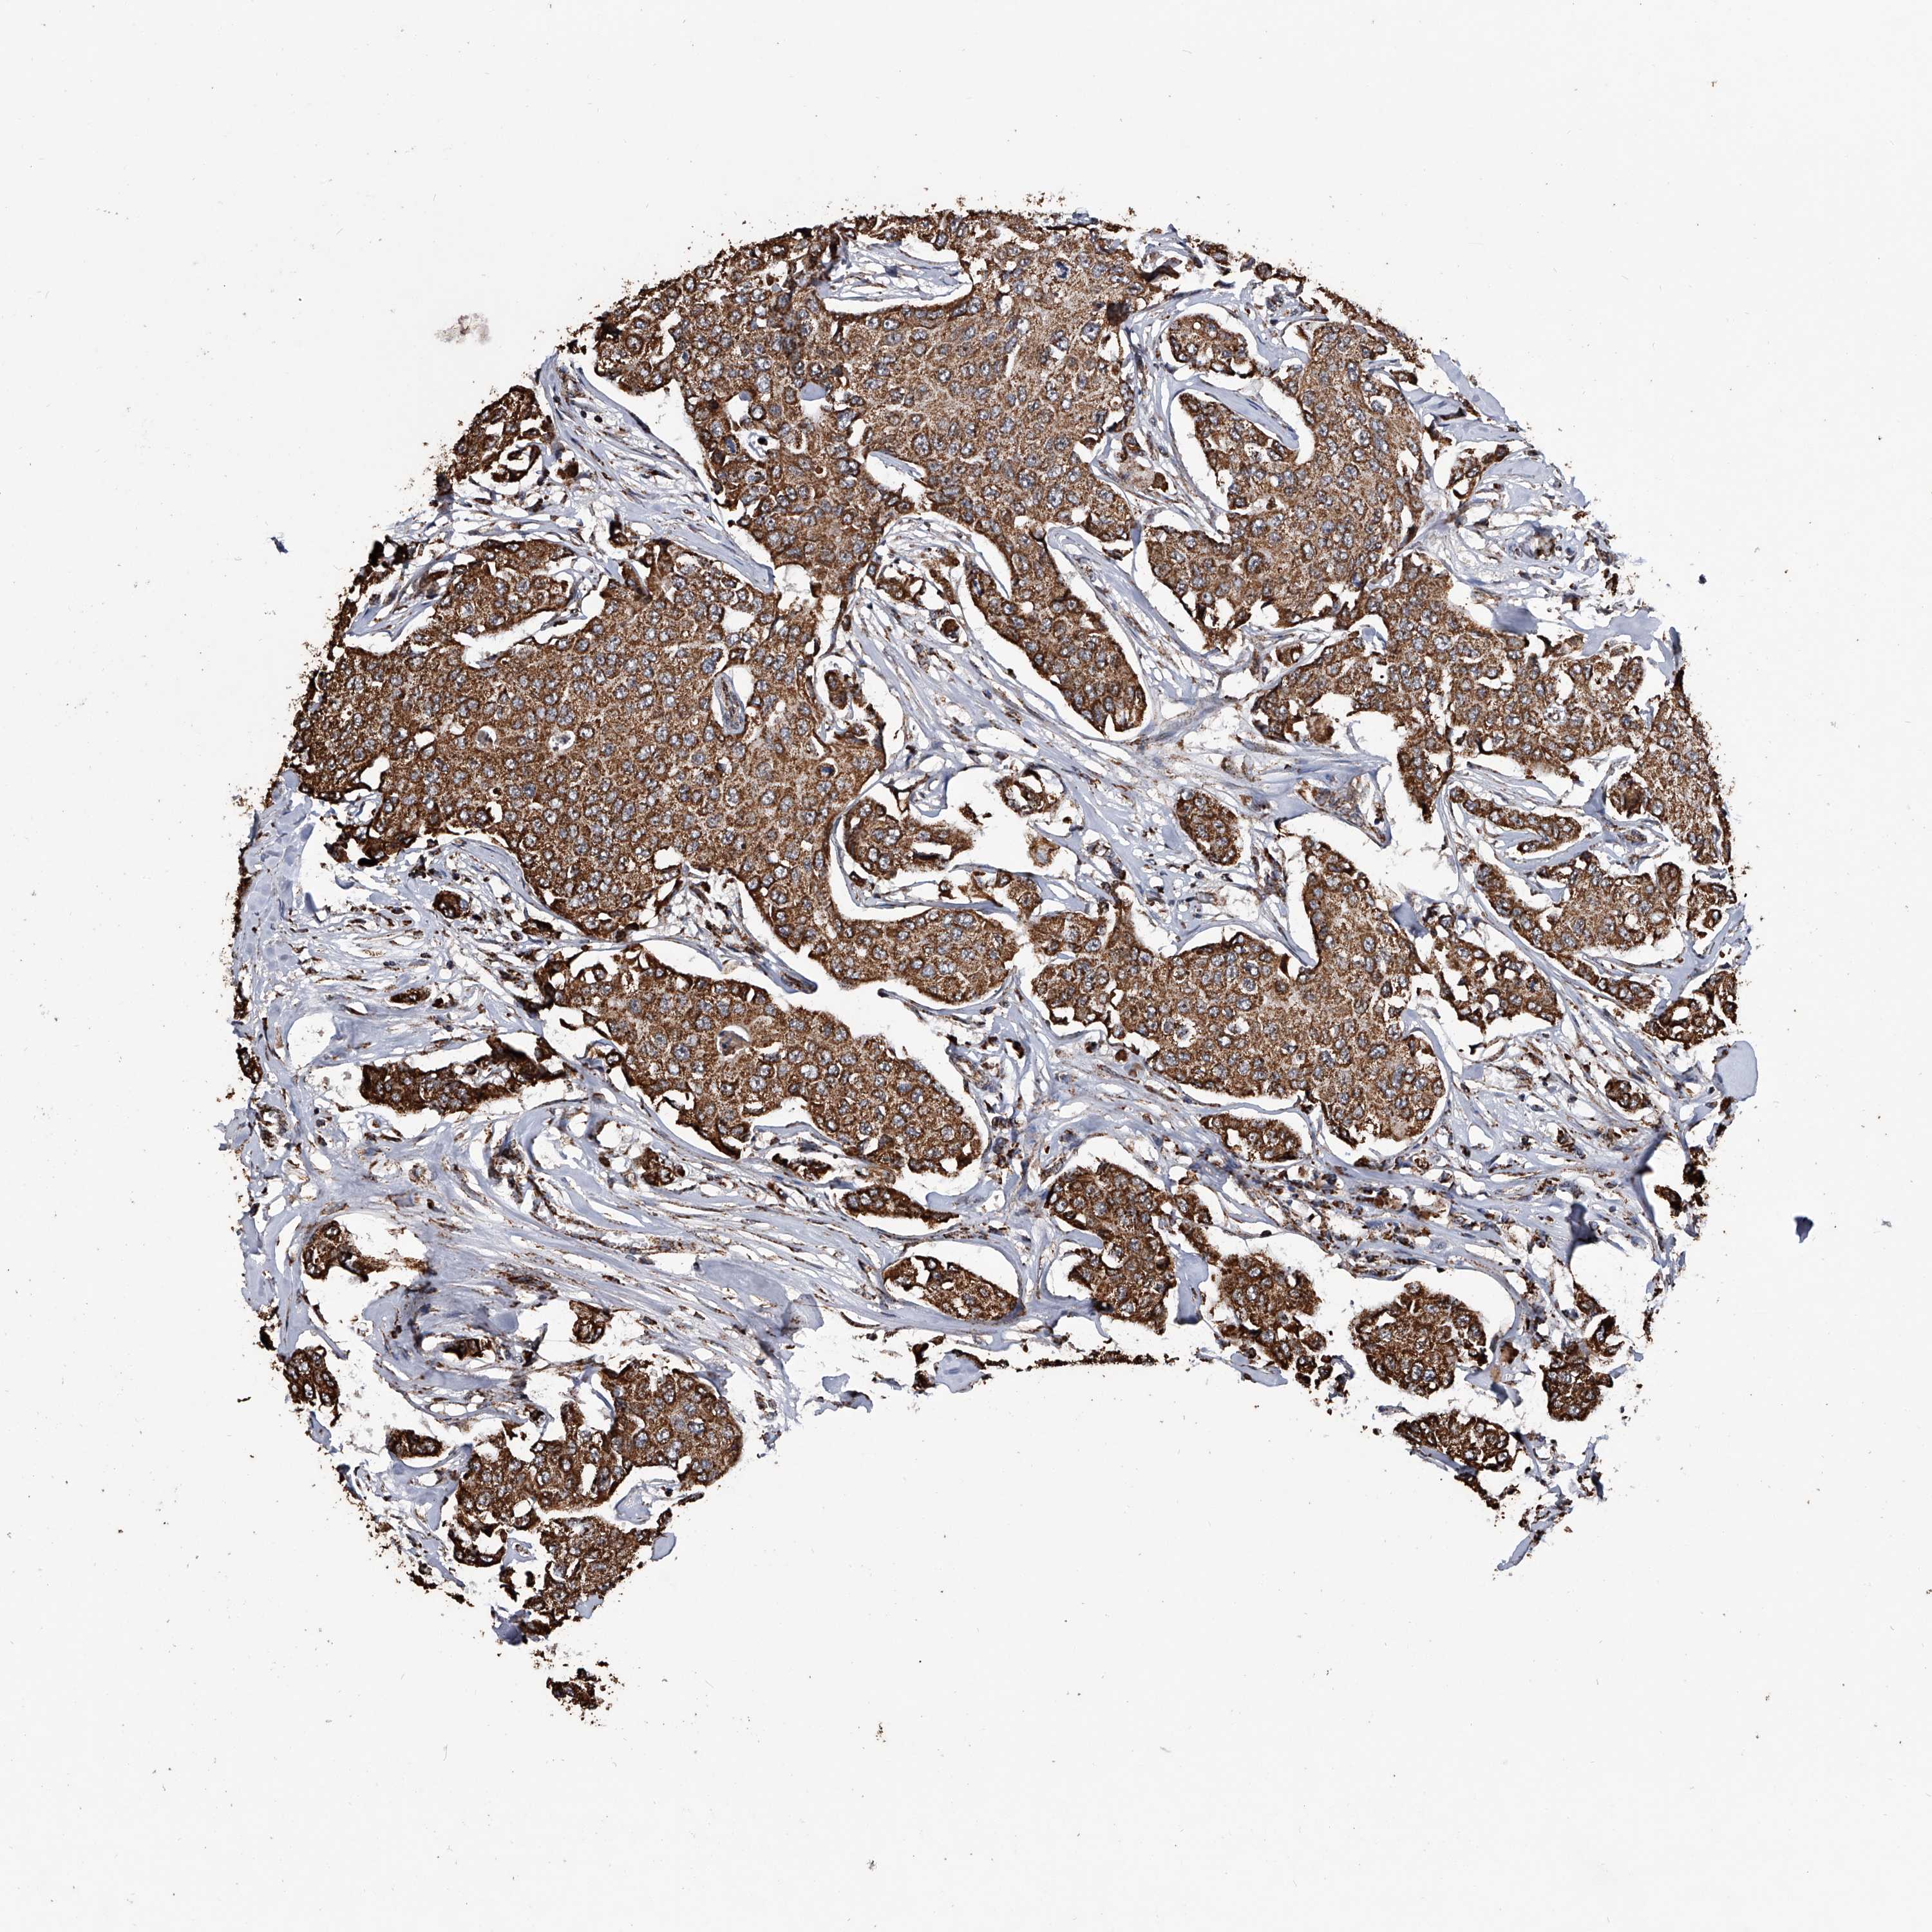

BRCA TCGA BRCA VALIDATION PROTEIN EXPRESSION